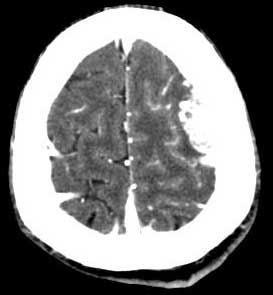

男,35岁。言语不清10余天,口角歪斜。

左颞部稍低密度d形肿块影阴,密度不均,内有不规则囊变区,局部脑白质受压塌陷,肿块周围少许水肿带,中线轻度右移位,增强扫描明显强化,局部颅板有轻微侵蚀,如此大的肿块中线结构移位不明显说明肿块位于脑外,如此强化的脑外肿瘤只有一个------脑膜瘤

平扫呈低密度,与颅内板接触广泛,脑皮层受压内移,增强明显强化,内示不规则的坏死区,周围脑实质内未见明显水肿.

脑膜瘤.

定位:脑灰白质界面内移,肿瘤位于脑外,应该明确。

定性:支持脑膜瘤。

左侧颞顶叶见d形肿块灶,密度不均,其内可见低密度影,局部脑白质所压移位,病灶明显强化。支持脑膜瘤